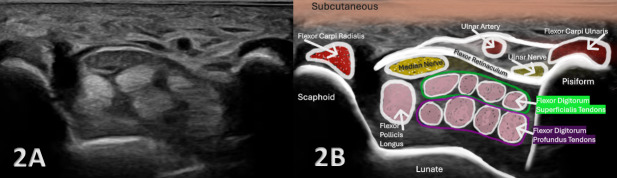

正中神经是前臂和手腕的重要结构,负责运动和感觉功能。神经损伤的准确诊断对于制定适当的治疗计划和优化患者预后至关重要。虽然磁共振成像(MRI)和神经传导研究(NCS)是神经评估的金标准,但诊断肌肉骨骼(MSK)超声提供了一种便携式、实时、经济高效的替代方法,在康复和运动医学领域越来越受欢迎。MSK超声已经成为评估正中神经病理的一种有价值的、非侵入性的成像方式,包括腕管综合征(CTS)、神经卡压和创伤性神经损伤。本文综述了MSK超声在评估正中神经损伤中的应用,包括其解剖、常见损伤模式、超声技术以及专业康复的临床意义。通过将MSK超声整合到临床实践中,提供者可以提高诊断的准确性,监测愈合进展,并指导康复策略以获得最佳患者结果。

The median nerve is a crucial structure in the forearm and wrist, responsible for motor and sensory functions. Accurate diagnosis of nerve injury is essential for appropriate treatment planning and optimizing patient outcomes. Although magnetic resonance imaging (MRI) and nerve conduction studies (NCS) are the gold standard for nerve assessment, diagnostic musculoskeletal (MSK) ultrasound offers a portable, real-time, and cost-effective alternative that is gaining traction in rehabilitation and sports medicine settings. MSK ultrasound has emerged as a valuable, non-invasive imaging modality for evaluating median nerve pathology, including carpal tunnel syndrome (CTS), nerve entrapment, and traumatic nerve injuries. This article reviews the utility of MSK ultrasound in evaluating the median nerve injury, including its anatomy, common injury patterns, sonographic techniques, and clinical implications for professional rehabilitation. By integrating MSK ultrasound into clinical practice, providers can improve the accuracy of diagnosis, monitor healing progression, and guide rehabilitation strategies for optimal patient outcomes.